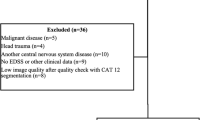

High-resolution structural MRI was acquired from 42 RRMS patients and 43 controls (HC). The patient group was dichotomized based on the presence versus absence of DIR-hyperintense cortex-involving lesions, resulting in a cortical lesion group (CL, n = 32) and a non-cortical lesion group (nCL, n =10). Cognitive functioning was assessed in all participants with a comprehensive neuropsychological battery, covering mnestic, executive, and attentional functions.

Forty-two patients with a diagnosis of relapsing-remitting multiple sclerosis (RRMS) according to the McDonald 2010 criteria [18] were recruited at the Multiple Sclerosis Centre of the University Hospital of Zurich. Patients with at least one DIR-hyperintense cortex-involving lesion were assigned to the cortical lesion group (CL group, n = 32), the remaining patients formed the non-cortical lesion group (nCL group, n = 10). All patients received immunomodulatory treatment - 30 with natalizumab, seven with beta-interferons, three with fingolimod, one with glatiramer acetat and one with dimethylfumarate. Exclusion criteria were a relapse or steroid-treatment during the last two months, current or past neurological disorders in addition to multiple sclerosis, and psychiatric disorders apart from MS-related depressive mood state. Moreover, none of the patients was affected by severe visual deficits or upper limb sensorimotor impairment that could hinder cognitive test performance. Furthermore, 43 age-, gender-, handedness- and education-matched healthy control persons (HC) without previous or present history of neurological or psychiatric diseases were included. Controls received financial compensation for their attendance.